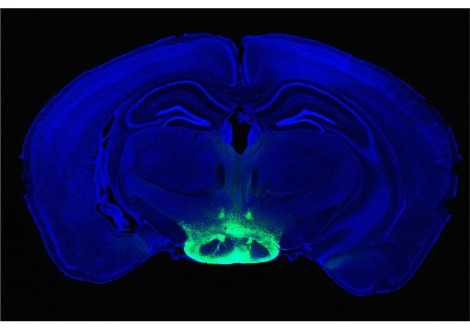

تعتبر اللويحات، وهي كتل خارج الخلية من بروتين AB42 في الدماغ، من العلامات الواضحة لمرض الزهايمر. الخلايا

البلعمية (والتي يشار إليها باسم الخلايا الدبقية الصغيرة عندما تكون موجودة في الدماغ)، وهي خلايا مناعية تبحث عن المواد

غير المرغوب فيها وتدمرها، تزيل AB42 من الدماغ عن طريق تناولها في عملية تسمى البلعمة. في بحث سابق، قام الدكتور

هيرلي وزملاؤه في الكلية الملكية للجراحين في أيرلندا بالتحقيق في التحكم اليومي في الخلايا البلعمية، وجمعوا مجموعة

بيانات شاملة جعلت من الممكن معرفة أي الحمض النووي الريبي والبروتينات في الخلايا البلعمية تتذبذب بإيقاع يومي. لاحظ

الباحثون تذبذبات في الإنزيمات التي تساعد في صنع بروتينين على سطح الخلايا البلعمية - بروتيوجليكان كبريتات الهيباران

وبروتيوجليكان كبريتات الكوندرويتين - وكلاهما معروف بلعبه دورًا في تنظيم إزالة AB42.

هل يمكن أن تكون هذه البروتيوجليكان على سطح الخلايا بمثابة رابط بين النظام اليومي ومرض الزهايمر؟ وفي سلسلة من

التجارب الأنيقة لاختبار هذه الفرضية، أثبت الفريق أن كمية AB42 التي تبتلعها الخلايا البلعمية السليمة تتذبذب مع إيقاع

الساعة البيولوجية اليومي. ولم يحدث هذا النمط في الخلايا البلعمية التي لا تحتوي على ساعة بيولوجية. كما قاموا بقياس

التذبذبات اليومية في مستويات بروتيوجليكان كبريتات الهيباران وبروتيوجليكان كبريتات الكوندرويتين المنتجة على سطح

الخلايا البلعمية ذات الدورات البيولوجية الصحية. وقد حدث ذروة تصفية AB42 عندما كان إنتاج بروتيوجليكان الخلايا

السطحية في أدنى مستوياته، وأدى إزالة هذه البروتيوجليكان إلى زيادة الابتلاع، مما يشير إلى أن البروتيوجليكان تمنع تصفية

AB42.